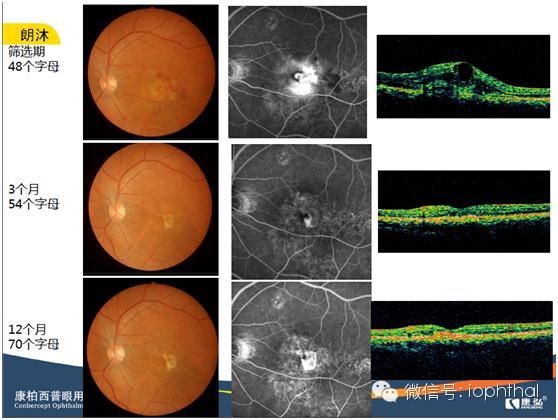

除湿性AMD外,康柏西普正在进行的临床注册试验还包括DME、病理性近视CNV和RVO等疾病,已有的研究结果表现出来的趋势令人充满期待,张风教授展示了部分典型病例的影像学结果(图2)。

图2. 湿性AMD应用康柏西普治疗的12个月结果